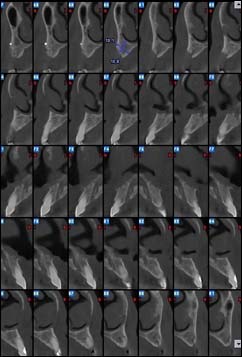

Examens tomographies volumiques type Scanner ou Cône beam

Dernière technologie à notre disposition, cette technique permet de voir en 3 dimensions des images de votre bouche et de mettre en évidence des pathologies ou des anomalies que les autres techniques ne permettent pas d’objectiver.

Coupe axiale

Reconstruction coronale